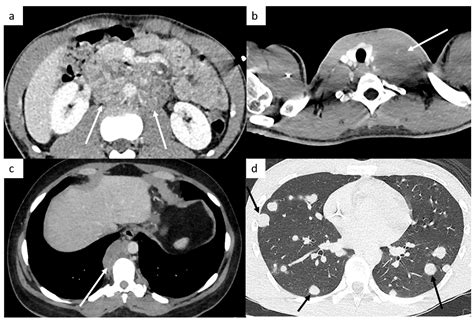

If you encounter something unusual, do not panic, but do not procrastinate. Seeking professional medical advice is the only way to get an accurate diagnosis. Doctors utilize several advanced diagnostic tools that go far beyond what a patient can see in testis cancer photos. Common diagnostic procedures include:

• Scrotal Ultrasound: This is the gold standard for imaging. It uses sound waves to create a detailed picture, allowing the doctor to see whether the mass is solid (potentially cancerous) or fluid-filled (usually benign).